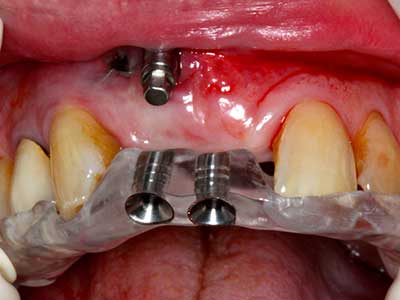

Индикация: Костно разделяне/ шиниране?

Костната тъкан е не само минерализирана структура, тя съдържа и съществено количество колагенови влакна. Това означава, че тя има не само добра компресивна сила, но и известна степен на гъвкавост, която може да се възприеме като предимство при извършване на костна аугментация. В класическата процедура по разширяване чрез костно разделяне, атрофиралият алвеоларен гребен е разделен надлъжно и внимателно разширен след достигане на подходящата остеотомна дълбочина (Фиг. 13-16), в идеалния случай без допълнително отстраняване на периостеума (Brugnami, Caiazzo et al. 2014, Stricker, Fleiner et al. 2014). Системите с винт и пластини с увеличаване на разстоянието при разширяване са доказали ефективността си при разделяне на двете костни ламели, оставайки под прага на фрактурите. В общи линии, оставащата ширина на костта от поне 3–4 mm е задължителна (Chiapasco, Zaniboni et al. 2006), за да се гарантира добра гъвкавост и достатъчно костно покритие за бъдещото поставяне на импланти. Ако е необходимо, вертикалната остеотомия на едната или двете страни може да подобри гъвкавостта. Комбинацията с допълнителни техники за аугментация, особено в букалната страна, е описана като алтернатива на класическата техника.

Процедурата по разделяне е атравматична и няма голяма загуба на пространство, използвайки пиезотриони, и няма значителна разлика между импланти в разделени челюсти и импланти в алвеоларния гребен без костен дефицит (Chiapasco, Zaniboni et al. 2006, Danza, Guidi et al. 2009). Въпреки това, важно е да има достатъчно и продължително охлаждане, особено при ограничено и дълбоко разделяне, за да се избегне термичен стрес в апикално-остеотомните зони.